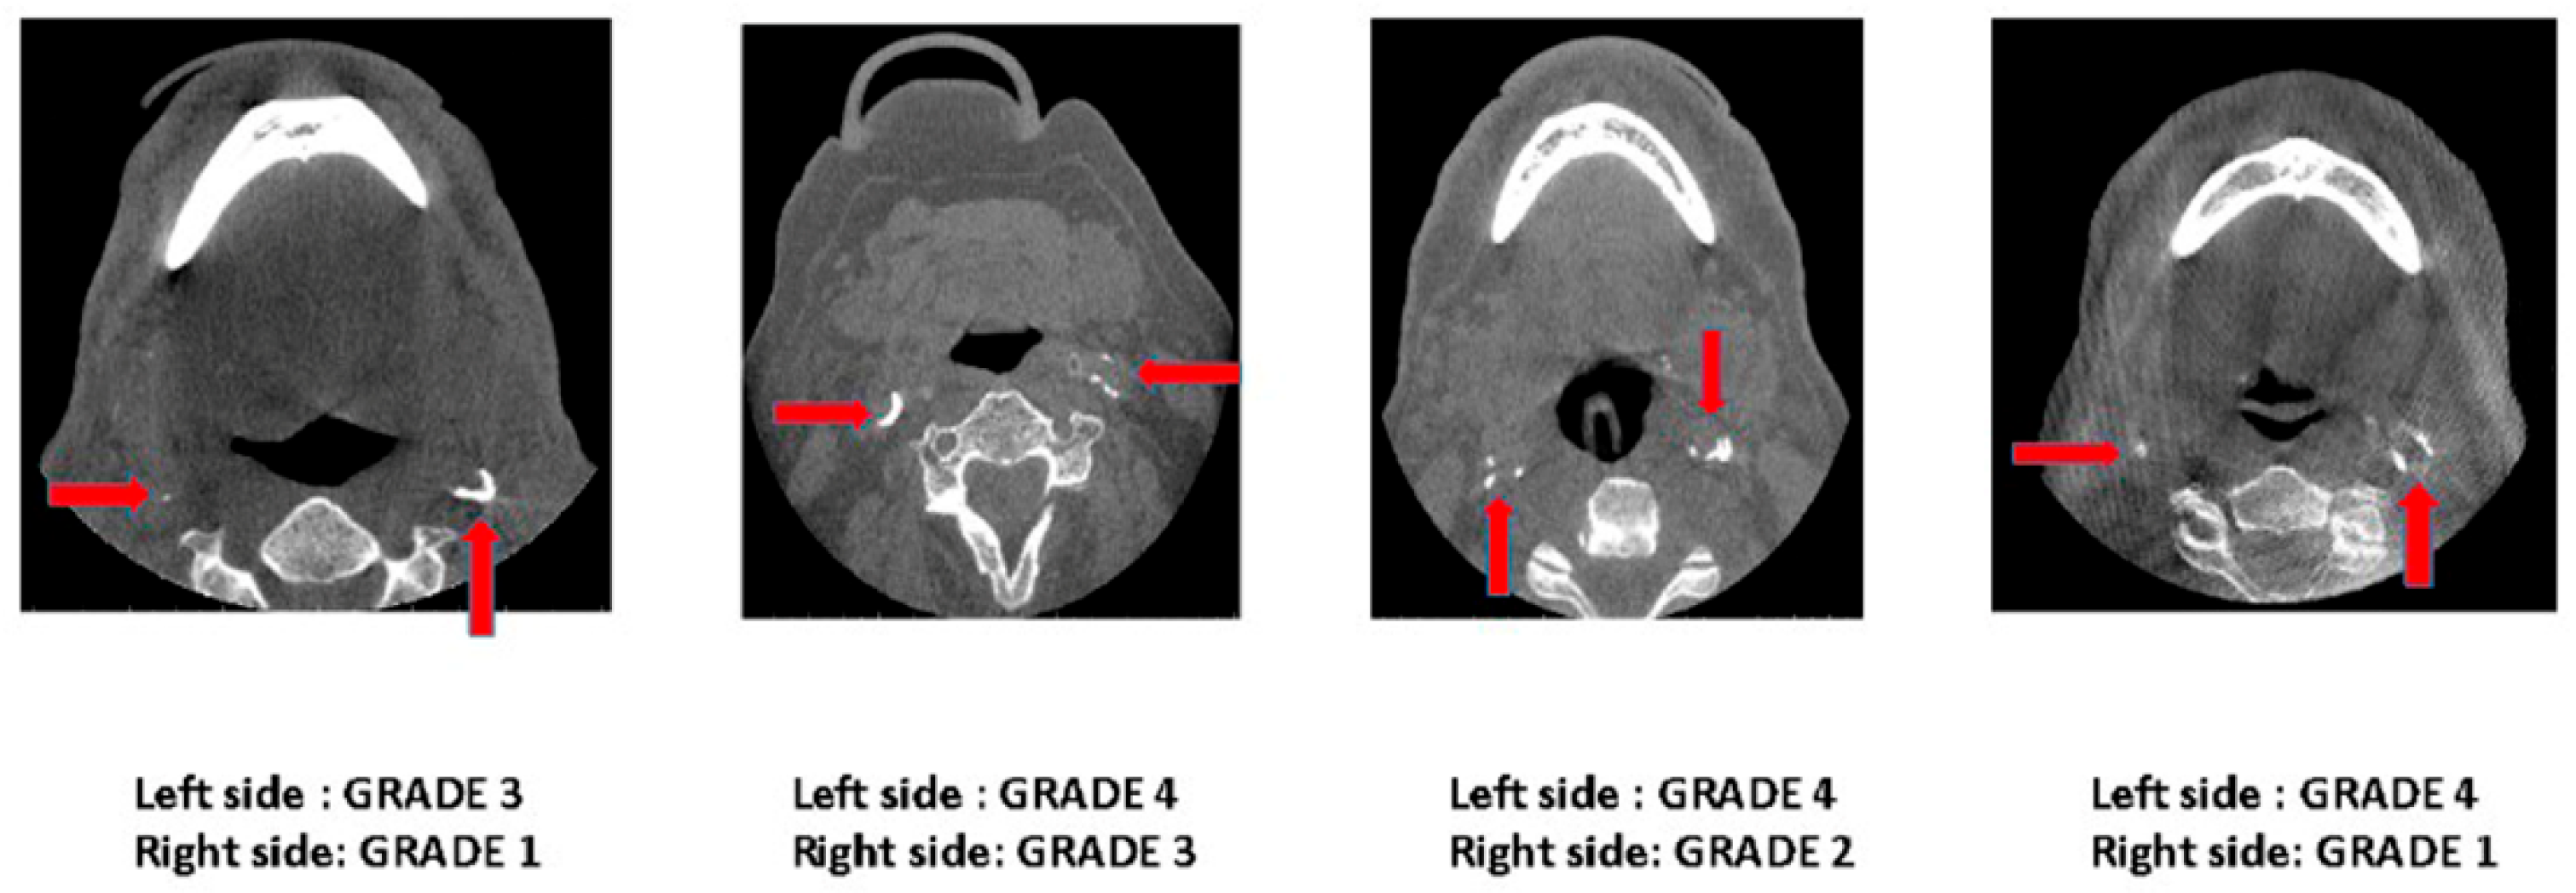

| Grade | Description |

|---|---|

| Grade 0 | No calcified plaque was present. |

| Grade 1 | Presence of a single speck of calcified plaque. |

| Grade 2 | Presence of more than one/multiple discontinuous specks of calcifications. |

| Grade 3 | One continuous semi-lunar band of calcification, covering at least half of the arterial lumen. |

| Grade 4 | One continuous semi-lunar band of calcification, covering at least half of the arterial lumen, along with one or more discontinuous calcified specks (Grade 2 + Grade 3). |

| Grade 5 | Circumferential coverage of the arterial lumen with calcified plaque. |